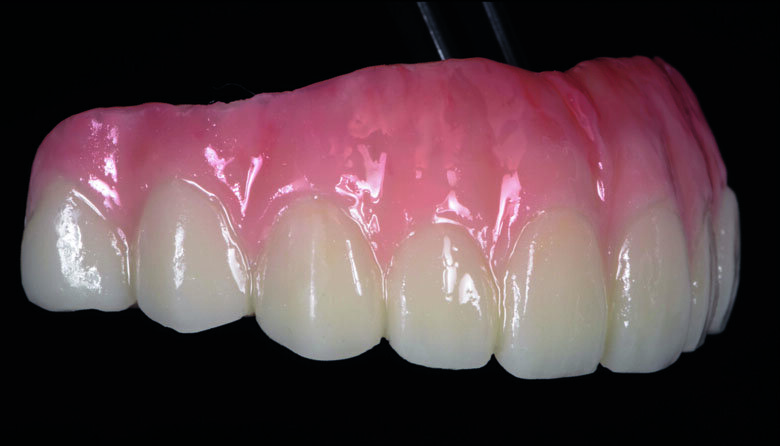

Fig 19. Completed Provisional Profile Prosthesis with gingival aesthetics that mimic nature

Preparation cast with a diagnostic wax-up ca st was sent to a local laboratory for scanning and transforming into STL (Stereolithography) digital impression file. (Fig 8,9.) Two sets of STL impressions were super-imposed in the software in order to subtract the overlapping data. This process was done in order to transform the diagnostic wax-up into the STL digital impression. Consequently, the STL data was sent to the laboratory for milling. (Fig10.) A monochromatic milled-PMMA temporary bridge was fabricated in a local laboratory and returned to the dentist for composite layering. (Fig 11.) Gingival cutback was made to create sufficient gingival space for pink composite layering (Fig 12). Prior to composite layering CeraResin Bond 1 was applied and left for 10 seconds to prime the surface, followed by application of CeraResin Bond 2 for 10 seconds and light cured for 20 seconds (Fig 13.). Ceramage Indirect Composite gingival shade GUM-O (GUM Opaque) was applied to mask the color of PMMA (Fig 14.). GUM-D (GUM Dark) was applied on the attached gingiva area to the buccal flange (Fig 15.). GUM-L (GUM Light) was applied in the region of free gingiva (Fig 16.). F-GUM-R (Flowable GUM Red) and F-W (Flowable GUM White) were painted to mimic the mucogingival junction and vascular alveolar mucosa (Fig 17.) GUM-T (GUM Translucent) was applied to reproduce of reddish translucent gingiva areas (Fig 18) to achieve natural gingival aesthetics.

Contouring, Finishing and Polishing of temporary restoration

Meticulous finishing and polishing of the restoration is a crucial step to achieving the desired aesthetics. Dura-Green stone was used to contour the macro anatomical details while the Robot Carbide Fissure Bur was used to shape the interproximal and papilla areas. The course silicone points followed by Dura-Polishing paste Al2O3 with a medium strong brush was used to finish and pre-polish the restoration. Dura-Polish DIA, diamond polishing paste was applied with a fine brush followed by the cotton buff to achieve the final high-luster polishing (Fig 19.)1.